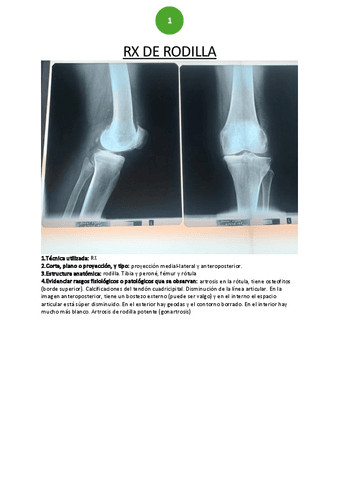

Prácticas - RX-cadera-y-rodilla.pdf

Prácticas - RX-rodilla.pdf

Apuntes - TEMA-8-TRAUMA-RODILLA-Y-PIERNA.pdf